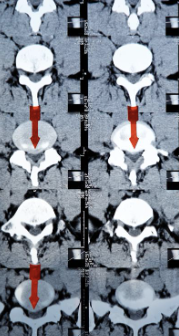

허리디스크는 디스크가 터져서 신경을 누를 경우 생기는 것으로 보통 4,5번에서 많이 발생하고 디스크가 터진 양이 적다면 터진 순간부터 수분이 날아가면서 양이 많이 없어지는데 그렇지 않고 양이 많을 경우 극심한 통증이 생깁니다.

통증이 덜한 환자들은 재활 , 물리, 약물치료 등을 통해 진행하지만 특정 원인이나 흘러나온 디스크가 신경을 많이 눌러 극심한 통증이 있다면 빠른 수술을 진행하는 것이 좋습니다.